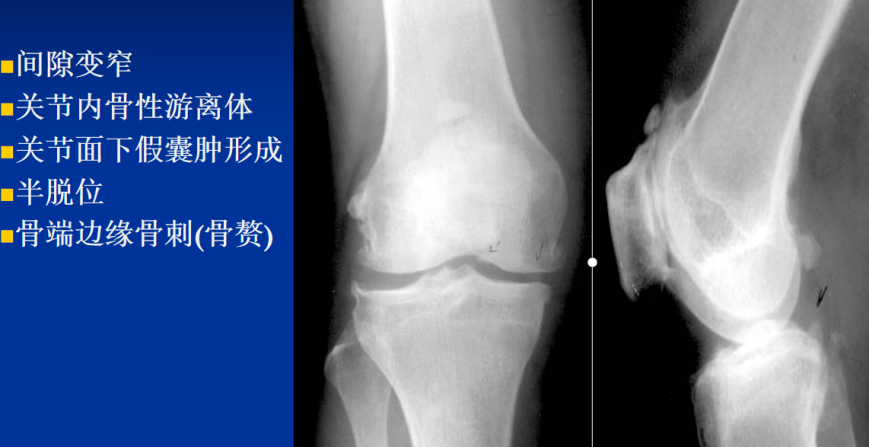

3.关节退行性变:缓慢发生的软骨变形、坏死、溶解,关节间隙变窄,继而骨性关节面增生、硬化,并于骨缘形成骨赘,X线表现:关节间隙狭窄、软骨下骨质囊变和骨性关节面边缘骨赘形成,老年人常见,慢性创伤和长期承重也可导致:脊柱,髋关节、膝关节为明显

1.退行性骨关节病

定义:关节软骨退行性改变所引起的慢性骨关节病。

承重关节如髋、膝和脊柱易受累

关节软骨退变,软骨表面不光滑,变薄,且可碎裂,游离于关节腔,关节面骨皮质暴露,骨皮质硬化,边缘形成骨赘。

X线表现:1、关节面边缘骨质增生,关节面硬化;2、关节面下方骨内出现圆形不规则透明区;3、关节间隙正常或狭窄;4、关节游离体形成